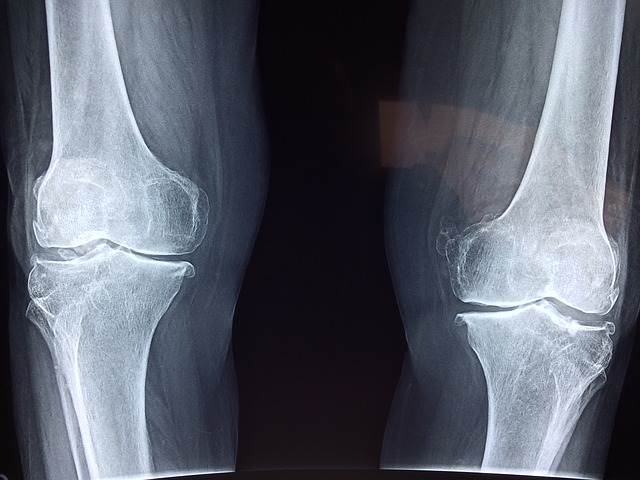

Každá bolest kloubů se musí řešit. Navštivte svého lékaře, který vás pošle na vyšetření a na základě nálezu stanoví léčbu. Obvykle se provádí rentgenové, CT vyšetření, magnetická rezonance a ultrazvuk. Léčba pak závisí na příčině. Lékař vám předepíše léky na bolest, pošle na fyzioterapii nebo doporučí operaci.